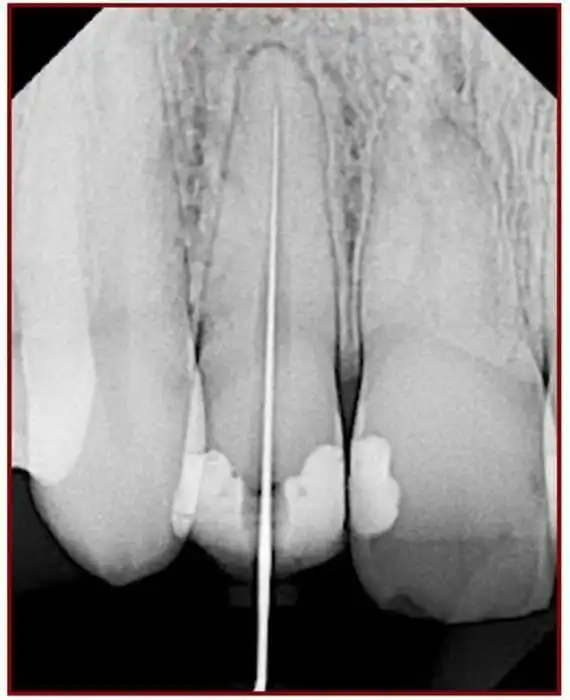

После того как \«нерв\» удалили наша первейшая задача определить какая же у канала длина. Ранее использовали рентгенологический способ — в канал засовывался файл и делался снимок, на котором было видно насколько глубоко этот файл отстоит от макушки.